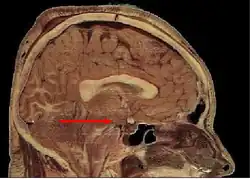

Гипотала́мус[1] (лат. hypothalamus, от др.-греч. ὑπό ‘под’ и θάλαμος ‘комната, камера, отсек, таламус’) — небольшая область в промежуточном мозге, включающая в себя большое число групп клеток (свыше 30 ядер)[2], которые регулируют нейроэндокринную деятельность мозга и гомеостаз организма. Гипоталамус связан нервными путями практически со всеми отделами центральной нервной системы, включая кору, гиппокамп, миндалину, мозжечок, ствол мозга и спинной мозг. Вместе с гипофизом гипоталамус образует гипоталамо-гипофизарную систему, в которой гипоталамус управляет выделением гормонов гипофиза и является центральным связующим звеном между нервной и эндокринной системами. Он выделяет гормоны и нейропептиды и регулирует такие функции, как ощущение голода и жажды, терморегуляция организма, половое поведение, сон и бодрствование (циркадные ритмы). Исследования последних лет показывают, что гипоталамус играет важную роль и в регуляции высших функций, таких как память и эмоциональное состояние, и тем самым участвует в формировании различных аспектов поведения.

Гипоталамус является частью промежуточного мозга. Он образует основание и стенки нижней части третьего желудочка. Название своё он получил от греч. гипо- (под, внизу) и таламос (чертог, спальня), так как он располагается под таламусом. Гипоталамус отделён от таламуса гипоталамической бороздой (лат. sulcus hypothalamicus). Анатомические границы гипоталамуса определены недостаточно чётко, что связано с тем, что некоторые группы клеток заходят в соседние области, а также с некоторой неопределённостью в терминологии[3]. Считается, что спереди (рострально) гипоталамус ограничен терминальной пластинкой (лат. lamina terminalis), а его задняя (каудальная) граница — воображаемая линия от задней комиссуры (лат. commissura posterior) до каудальной поверхности сосцевидных тел. Дорсолатерально гипоталамус доходит до медиального края мозолистого тела[4].